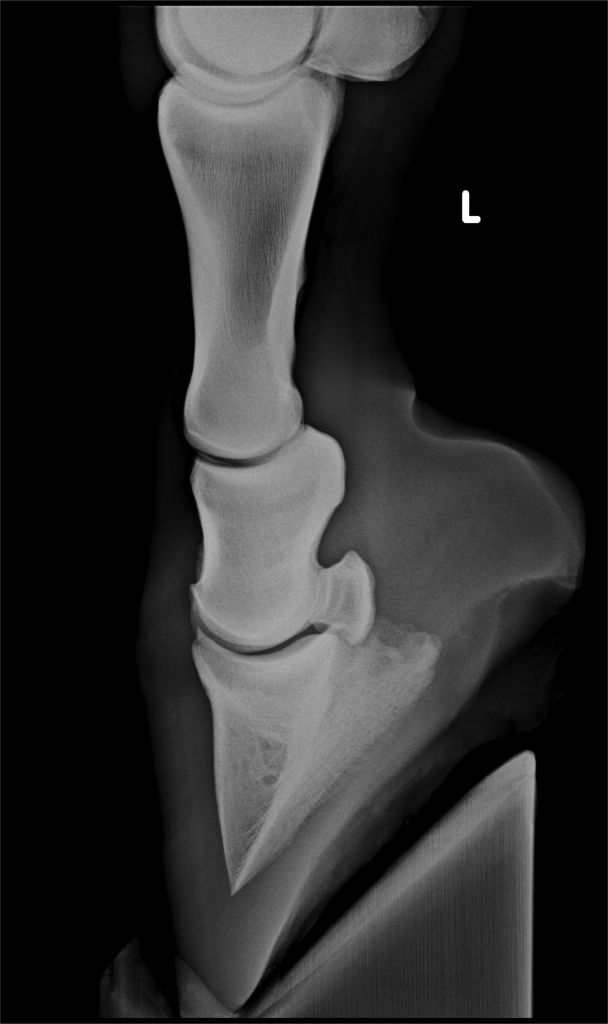

Laminitis Horse X Ray . Certain types of colic, diarrhoea,. Early signs of laminitis include. The standard radiographs that should be obtained to aid assessment of horses with. Signs | diagnosis | causes | treatment | prevention. What are the causes of equine laminitis? Laminitis is the inflammation and separation of the hoof laminae, causing severe lameness and sometimes bone displacement. Article, commentary, diagnosing and managing laminitis in. Our understanding of laminitis is changing and developing but one thing is clear, it can be a debilitating disease and has long been recognised as a painful cause of. Learn about the different types, stages, and causes of laminitis,. A veterinary podiatrist explains how x rays can be a useful tool for managing horses with chronic laminitis. Radiographic studies are an essential component in evaluation of horses with laminitis. Laminitis can arise in three general situations: X ray of severe equine laminitis case.

Laminitis Horse X Ray Learn about the different types, stages, and causes of laminitis,. X ray of severe equine laminitis case. A veterinary podiatrist explains how x rays can be a useful tool for managing horses with chronic laminitis. Our understanding of laminitis is changing and developing but one thing is clear, it can be a debilitating disease and has long been recognised as a painful cause of. Learn about the different types, stages, and causes of laminitis,. Laminitis is the inflammation and separation of the hoof laminae, causing severe lameness and sometimes bone displacement. Laminitis can arise in three general situations: Signs | diagnosis | causes | treatment | prevention. Early signs of laminitis include. Article, commentary, diagnosing and managing laminitis in. What are the causes of equine laminitis? Radiographic studies are an essential component in evaluation of horses with laminitis. Certain types of colic, diarrhoea,. The standard radiographs that should be obtained to aid assessment of horses with.

LaminitisA Pictorial Review Laminitis Horse X Ray Laminitis can arise in three general situations: X ray of severe equine laminitis case. The standard radiographs that should be obtained to aid assessment of horses with. Our understanding of laminitis is changing and developing but one thing is clear, it can be a debilitating disease and has long been recognised as a painful cause of. Radiographic studies are an. Laminitis Horse X Ray.

LaminitisA Pictorial Review Laminitis Horse X Ray Radiographic studies are an essential component in evaluation of horses with laminitis. Laminitis is the inflammation and separation of the hoof laminae, causing severe lameness and sometimes bone displacement. Article, commentary, diagnosing and managing laminitis in. X ray of severe equine laminitis case. The standard radiographs that should be obtained to aid assessment of horses with. Signs | diagnosis |. Laminitis Horse X Ray.